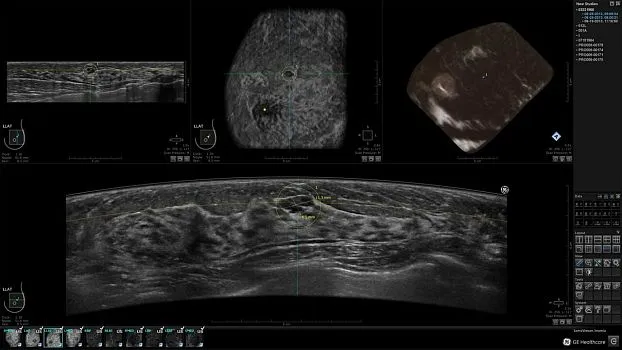

Клинические изображения

Ультразвуковая система для автоматизированного сканирования молочных желёз Invenia ABUS — это удобная, неионизирующая методика дополнительного скрининга молочных желёз у женщин с повышенной плотностью ткани. При плотной молочной железе традиционная маммография может пропустить более 1/3 раковых опухолей. Использование же Invenia ABUS в дополнение к маммографии может улучшить обнаружение инвазивного рака на 55% по сравнению с проведением только лишь одной маммографии.

• Получение объемных 3D изображений с возможностью покадрового просмотра

• Получение изображений:

• Поперечная плоскость (в реальном времени)

• Коронарная плоскость (статическая, для указания нахождения соска)

• Отображение объемных 3D ультразвуковых изображений, которые состоят из традиционных поперечных и воссозданных коронарных и сагиттальных проекций